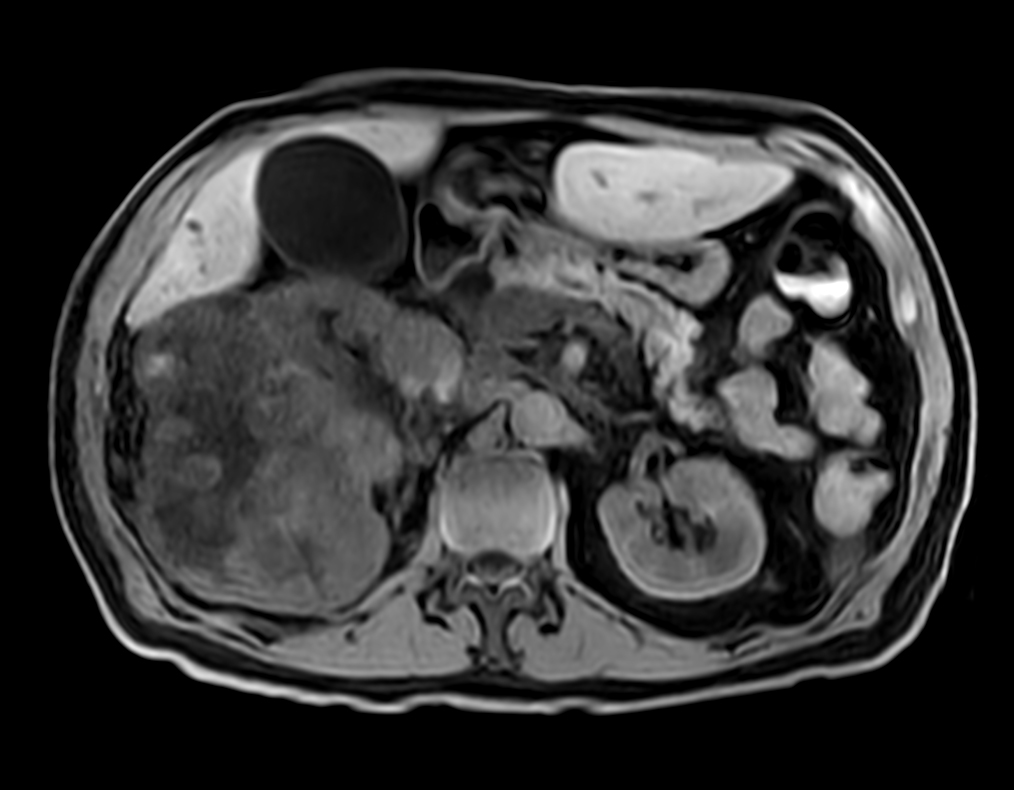

Patient with kidney tumor. ExamCard includes Compressed SENSE to shorten the breath hold time, VitalEye for touchless respiratory sensing, mDIXON XD FFE to acquire up to four image types in one single scan, DWIBS to achieve high contrast between background and lesions and bTRANCE for non-contrast time-resolved imaging.

T2w SPAIR - VitalEye Compressed SENSE